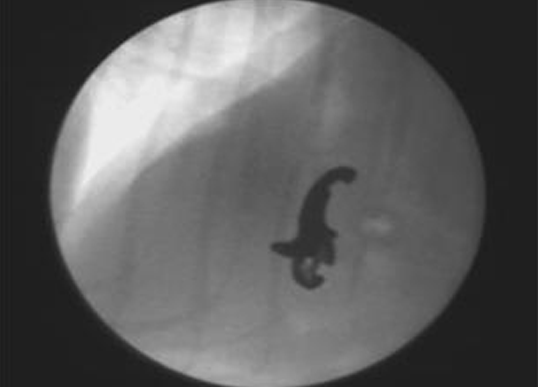

기관, 식도, 위장, 신장검사를 통해 실시간 영상 획득과 입체적인 구조를 파악할 수 있는 진단방법입니다. 투시 검사는 연속적인 X-선 방사를 통하여 실시간으로 영상을 획득하는 검사를 말합니다. 실시간 영상을 통해 소형견에서 다발하는 기관 협착증(Tracheal collapse)을 손쉽게 확인할 수 있으며 인후두부질병을 감별할 수 있습니다. 또한 조영촬영시 투시검사를 병행하여 식도나 위장관의 이물 형태와 위치를 입체적으로 파악할 수 있습니다.